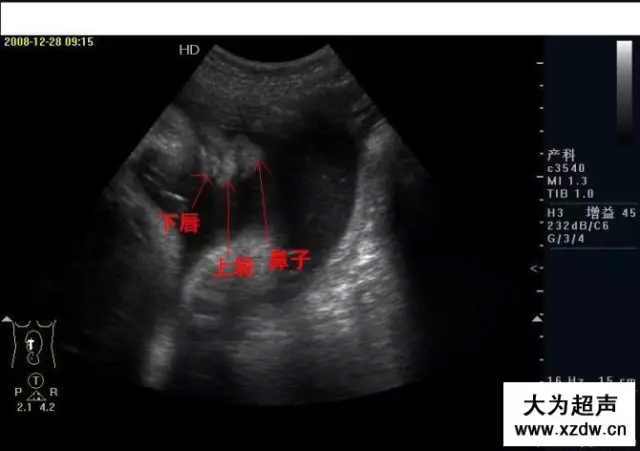

產科超聲正常圖片